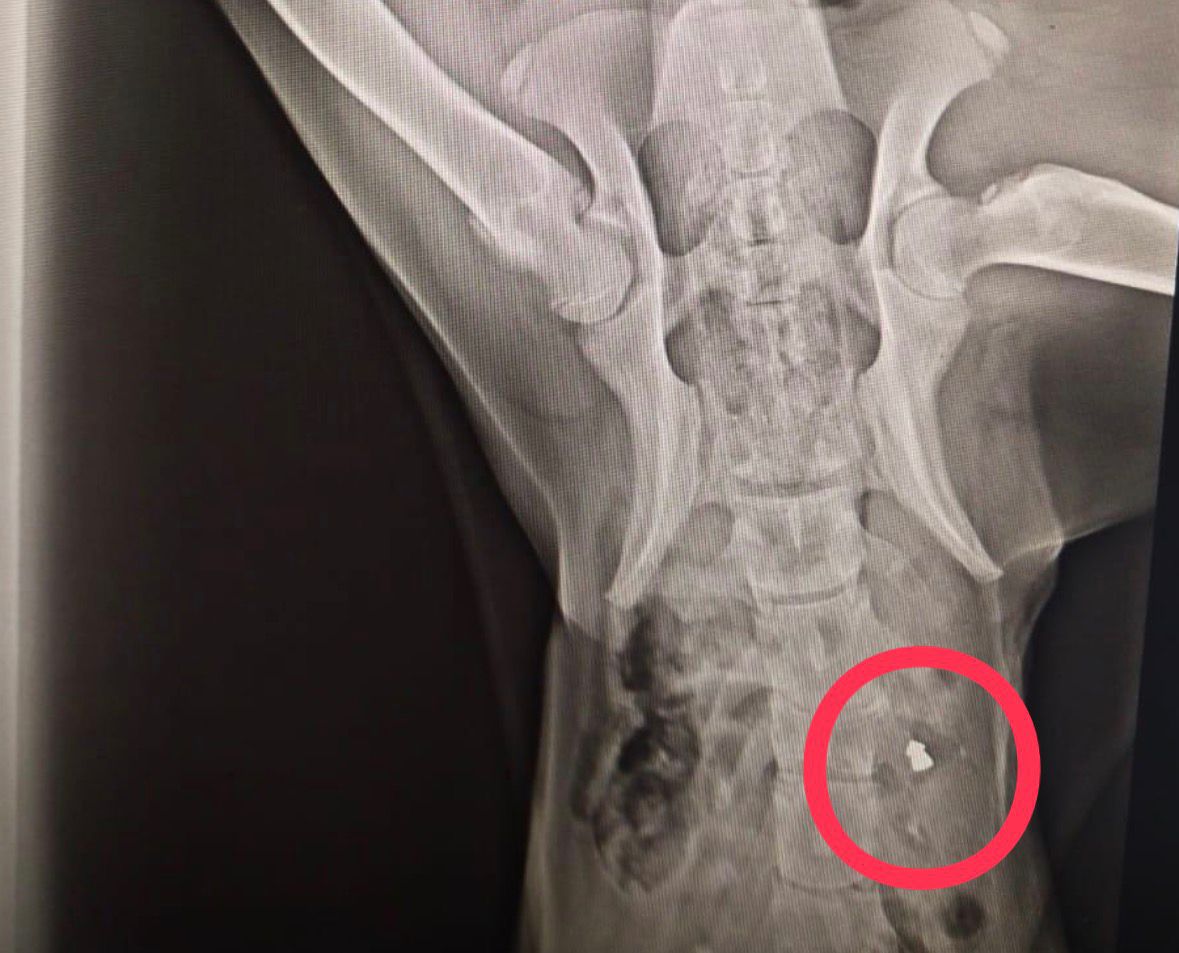

Perşembe ilçesi Efirli Mahallesi’nde biri bugün olmak üzere son 10 gün içerisinde ‘domuz kurşunu’ ile vurulmuş halde yaralı bulunan 3 sokak köpeği, tedavi edilmek üzere hayvanseverler tarafından Altınordu ilçesindeki Veteriner Hekim Taner Canbulut’a ait kliniğe getirildi. Burada yapılan kontrollerde, 3 köpeğin de vücutlarının çeşitli yerlerinde ‘domuz kurşunu’ tespit edildi. Bu süreçte kliniğe getirilen yaralı köpeklerden 2’sinin öldüğünü ve birinin ise tedavisinin devam ettiğini belirten Canbulut, “Son günlerde sokak canlarının tüfekle vurulması durumuyla karşı karşıyayız. 10 gün önce sırt bölgesinden vurulmuş bir köpek getirildi ve müdahale etmemize rağmen kurtaramadık. Bu olaydan kısa bir süre sonra aynı şekilde vurulmuş bir köpek daha buraya getirildi. Getiren hayvanseverler, otomobil çarpması sanmış ama burada tedavi ederken onun da aynı şekilde domuz kurşunu ile vurulmuş olduğunu tespit ettik. Kurşunu çıkardık ve şu anda durumu iyi. Bugün ise domuz kurşunu ile vurulmuş başka bir köpek daha getirildi. Maalesef felç olmuş ve kurtarılma şansı yoktu. Bu nedenle uyutmak zorunda kaldık. Çok üzgünüz. Bunu yapan kişi veya kişilerin yakalanmasını istiyoruz. Bu yapılanlara ‘dur’ denmesi gerekiyor. Bu hepimizin insani, vicdani ve ahlaki vazifesi diye düşünüyoruz” dedi.